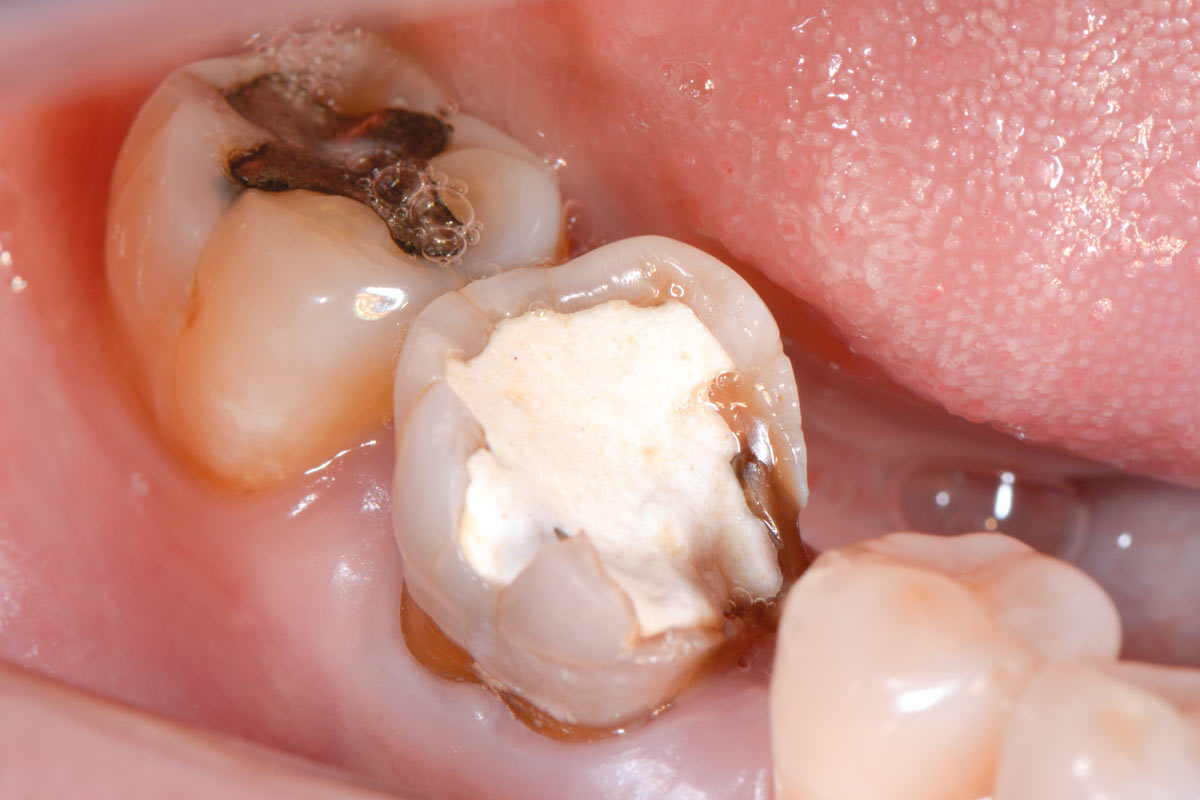

4/19 - Initial clinical situation before extraction and implantation

Immediate implant placement using maxresorb® - Dr. Alejandro Signorio

5/19 - Initial clinical situation before extraction and implantation